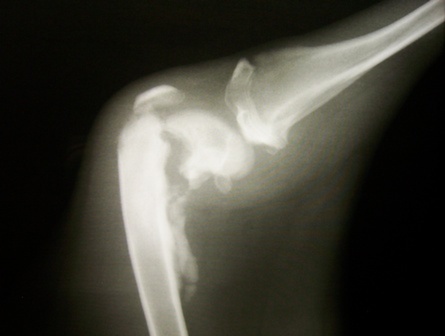

Sünit, a 11hónapos Belga Juhász keverék nőstény kölyköt törött lábbal mentettük ki 2010 őszén az Illatos útról.

Január közepére Süni felépült és elvégeztettük ivartalanítását is.

Már összebarátkozott a család másik kutyusával is és jövő héten kezdi a helyi orvos által is javasolt mozgásterápiát. Természetesen tartjuk a kapcsolatot az új gazdival.